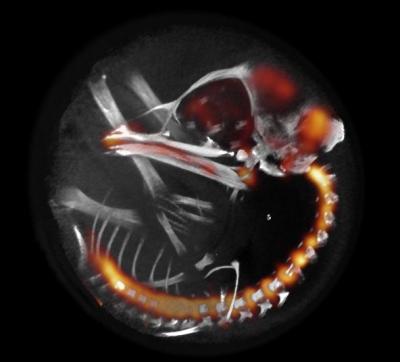

In order to carry out this study, a technique in which "Spain is a pioneer", according to the scientists, was adapted. This technique combines sub millimeter-resolution brain positron emission tomography (PET) and structural X-ray computed tomography (CT), creating a non-invasive technique that provides three-dimensional images of brain function in animal models, with sub-millimetric resolution. "For the first time, we have designed a procedure which allows us to observe and measure the changes in the embryo's brain activity as it vacillates between sleep and awake phases, without interfering in its normal development," comments Juan José Vaquero, of UC3M's Bioengineering Department.